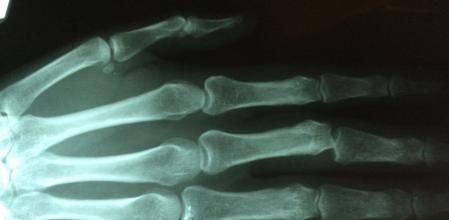

La factura correspondía principalmente a una radiografía, por lo que Osman decidió crear su propia máquina de rayos X para no tener que hacer frente nunca más a unas sumas tan elevadas de dinero, lo que le llevó a la siguiente pregunta: ¿podría fabricar su propia máquina de rayos X por un precio más barato de lo que le cobraron?

Para ello usó: un tubo de rayos X de 115 dólares, que consiguió de una máquina de rayos X dental rota que compró en eBay; un rollo gigante de hoja de plomo; varios contenedores Geiger y un suministro eléctrico capaz de suministrar hasta 60.000 voltios.

El resultado fue un éxito, la construcción de su propia máquina de rayos X le costó mucho menos que la factura de una sola radiografía en el hospital. Eso sí, el propio Osman ha querido advertir de los peligros de hacerse radiografías en casa: "¿Quieres llenarte de radiación?", y añadía que "Este es el artilugio más peligroso que he construido".